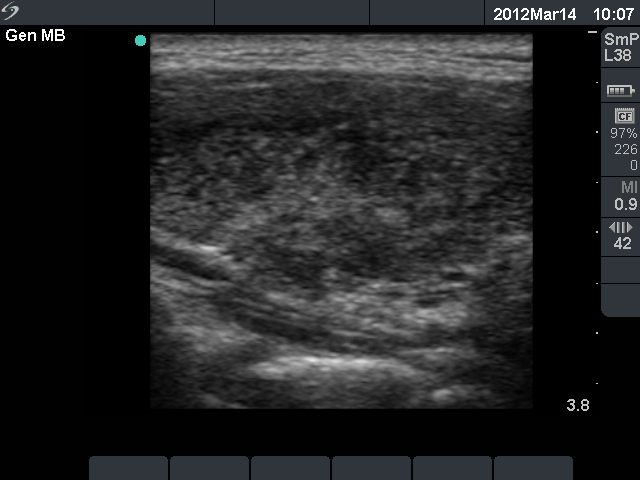

One year after radioiodine therapy (third row):

Clinical presentation: the patient had no complaints.

Palpation: the thyroid could not be palpated.

Functional state: mild hypothyroidism on daily 112.5 microgram levo-tiroxine (TSH-level 5.11 mIU/L).

Ultrasonography: the thyroids were hypoechogenic and presented extensive fibrosis. The size of the lobes decreased significantly. The thyroid presented no and decreased vascularization, right and left lobe, respectively.

Suggestion to increase the dose of levo-tiroxine to daily 125 microgram.